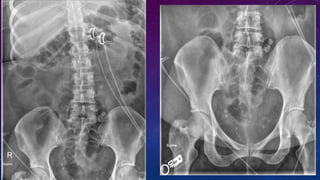

VAS DEFERENS CALCIFICATION

CASE 2

• Failed kidney transplant

• Seminal vesicle / vas deferens calcification

PRE TRANSPLANT

EVALUATION

FAILED BILATERAL RENAL TRANSPLANTS

CALCIFICATION